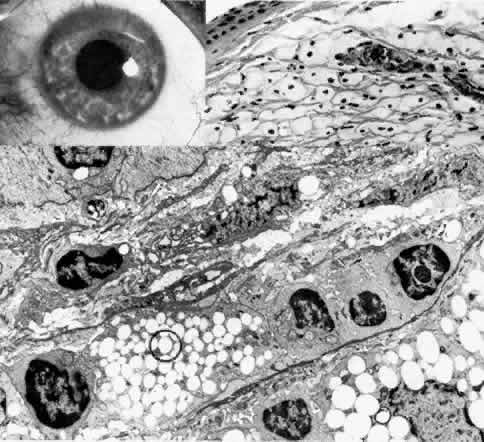

Fig. 4. Sclerocornea. Schematic drawing of ocular features Top left. In a minimally affected patient with additional findings of ptosis, strabismus, and hearing loss, only the peripheral cornea is opacified. Top center. In this advanced case with chromosomal translocation and multiple congenital abnormalities, the entire cornea is sclerified and the fine vascular arcades extend centrally from the conjunctiva and sclera. Top right. Light micrograph of anterior cornea shows edematous disorganization of epithelium, fragmentation of Bowman's membrane (B), and interstitial vascularization (V) (hematoxylin-eosin, × 200). Middle left. Transmission electron micrograph of normal human corneal stroma is shown for comparative purposes. Note uniform 240- to 260-nm collagen fibril diameter (× 50,000). Middle right. Transmission electron micrograph of sclerocornea at same magnification shows disorganized array of collagen fibrils that measure as much as three times normal diameter (× 50,000). Bottom. Transmission electron micrograph of posterior cornea shows abnormal Descemet's membrane of less than 1μm thickness (DM, bracketed) and attenuated endothelial cells (× 10,500). (Schematic. Grayson M: Diseases of the Cornea, p 32. St. Louis, CV Mosby, 1979; Top center and right. Rodrigues MM, Calhoun J, Weinreb S: Sclerocornea with an unbalanced translocation [17p, 10q]. Am J Ophthalmol 78:49, 1974)

Ultrastructural studies22,46,47 have shown the involved stroma to assume the morphologic features of scleral tissue, with irregularly arranged collagen fibrils of variable and immensely enlarged diameter for corneal tissue (up to 150 nm, comparable to normal scleral collagen). The precise lamellar organization of normal corneal stroma is not present; thus optical clarity is not achieved. Various abnormalities of endothelium and Descemet's membrane exist, from attenuation to focal absence. Descemet's membrane is generally thin, with multilaminar deposition of basement membrane-like collagen.